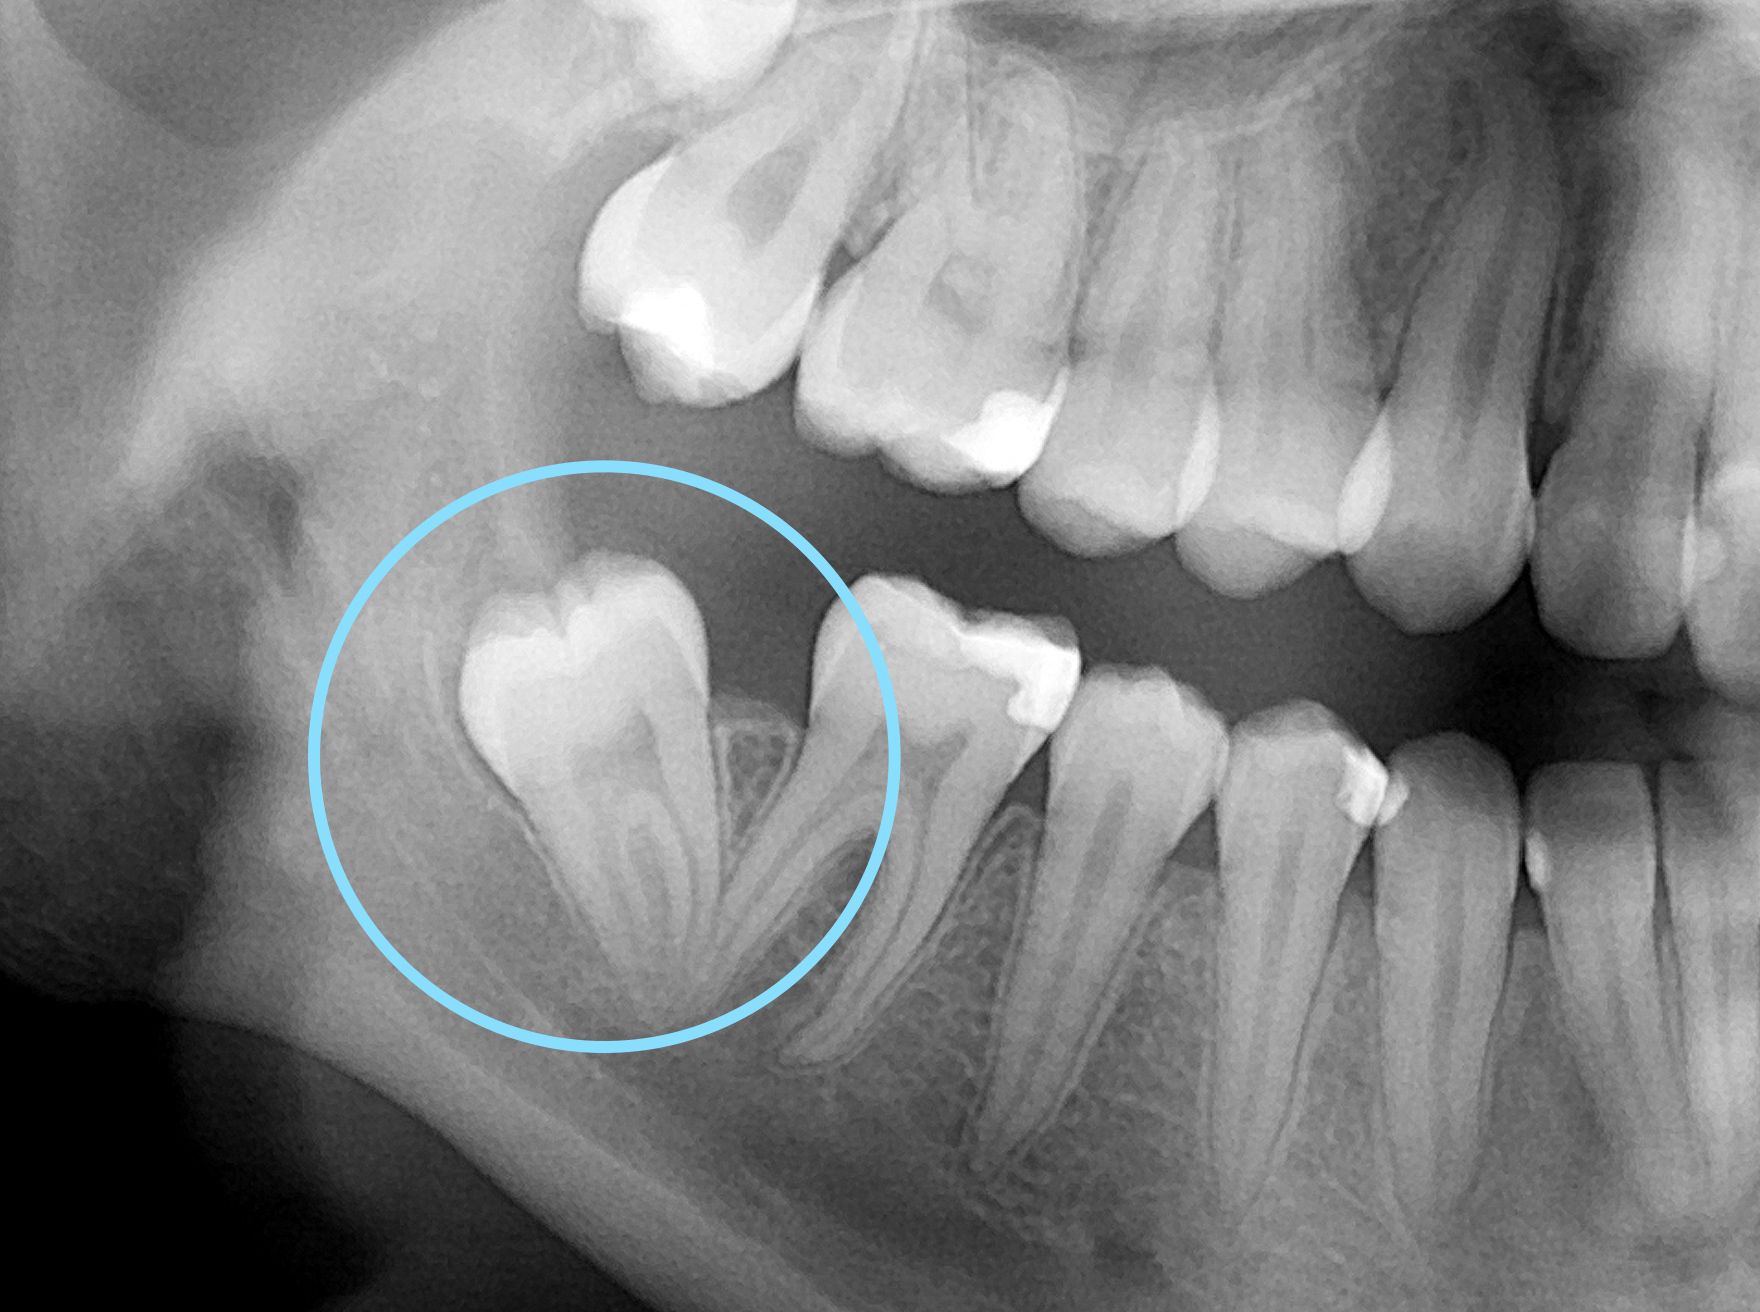

Trou Dans La Dent De Sagesse. Le Trou Dans La Dent Et Le Traitement Des Canaux Dentaires Traitement De Periodontitis Dans La L'extraction des dents de sagesse est une intervention chirurgicale courante qui peut laisser une cavité, un "trou", dans la gencive Cette situation soulève de nombreuses interrogations : pourquoi ce trou ne se referme-t-il pas comme on l'attendrait ?

Les symptômes à surveiller Pour déterminer si un trou de dent de sagesse ne se referme pas dans des conditions normales, il est crucial d'observer certains symptômes Les dents de sagesse, ces fameuses molaires qui font souvent parler d'elles, peuvent être à l'origine de divers désagréments

Les dents de sagesse Dentistes de la Cité. Découvrez les complications possibles liées à un trou de dent de sagesse qui ne se referme pas La cicatrisation de cette zone est cruciale pour prévenir les complications et retrouver une bouche saine

Ce qu’il faut savoir sur la dent de sagesse incluse Ilajak médical. Ces dents ne sont pas toujours les bienvenues, car elles peuvent causer des problèmes tels que des caries, des kystes et des infections, conduisant parfois à l'extraction et la création de. obtenez des informations détaillées sur les soins dentaires et les solutions disponibles.